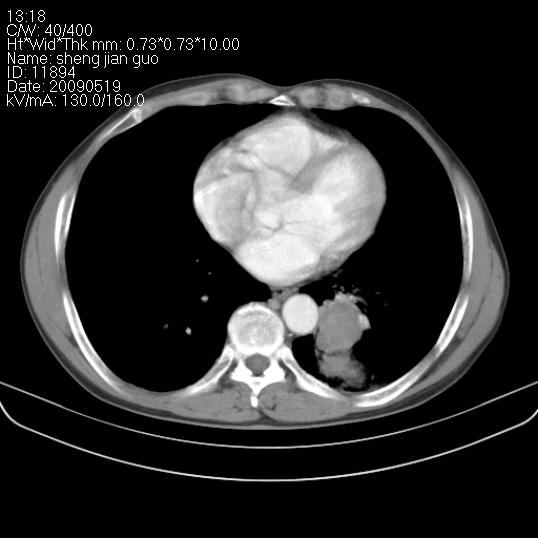

以下是引用zjzjr在2009-5-19 17:25:00的发言:[br]支持楼主考虑,另左肺下叶阻塞性炎症。

以下是引用zhao_bin2008在2009-5-19 17:48:00的发言:[br]支持左肺下叶周围型肺癌并阻塞性肺炎。

以下是引用zsl6918在2009-5-20 7:10:00的发言:[br]左侧中心型肺癌!